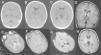

El análisis del líquido cefalorraquídeo (LCR) mostró proteínas de 1.192mg/dl, glucosa normal y 5 células (al día siguiente, las proteínas eran de 1.400mg/dl). La tomografía computarizada (TC) craneal mostró hipoatenuación de ambos tálamos y mesencéfalo (fig. 2). El electroencefalograma (EEG) durante las primeras 24h de la encefalopatía mostró discreto enlentecimiento de la actividad de fondo, sin actividad paroxística. Las proteínas totales en suero eran de 5,9g/dl el día del ingreso (6,6 a 8,7); de 5,4g/dl al día siguiente y, tras una semana, de 5,1g/dl. La alanina-aminotransferasa (ALT) era de 53 (5 a 45)U/l. Se inició tratamiento con vitaminas B1, B2, B6, biotina, B12 y carnitina.

A-C) Tomografía computarizada craneal (durante las primeras 24h): hipoatenuación de los ganglios basales, tálamos y mesencéfalo, más marcada en sustancia gris periacueductal, junto con dilatación de astas temporales de ventrículos laterales y acueducto de Silvio. D-G) Resonancia magnética (RM) craneal a los 3 días de ingreso: se aprecia hiperintensidad de la señal en ambos tálamos posteromediales en secuencia ponderada en T1, T2, DP y en secuencia de difusión. No hay dilatación del sistema ventricular ni alteración de la señal en ganglios basales ni mesencéfalo. H) RM craneal realizada 6 semanas después del episodio de encefalopatía, imagen axial en secuencia ponderada en T1 a la altura de los ganglios de la base y los tálamos: resolución de las alteraciones previamente descritas. Estudio sin hallazgos de significado patológico.

Después de 3 días, el nivel de consciencia era normal y no presentaba focalidad neurológica. Una RM craneal en ese momento mostró hiperintensidad de la señal en ambos tálamos posteromediales en las secuencias T1, T2, DP, FLAIR y difusión (fig. 2). Se excluyó trombosis de venas cerebrales profundas y de senos durales mediante angiografía por RM.

Tras este episodio de encefalopatía, el lactante se recuperó aparentemente sin secuelas. Una segunda RM craneal realizada 6 semanas después del episodio de encefalopatía fue normal.